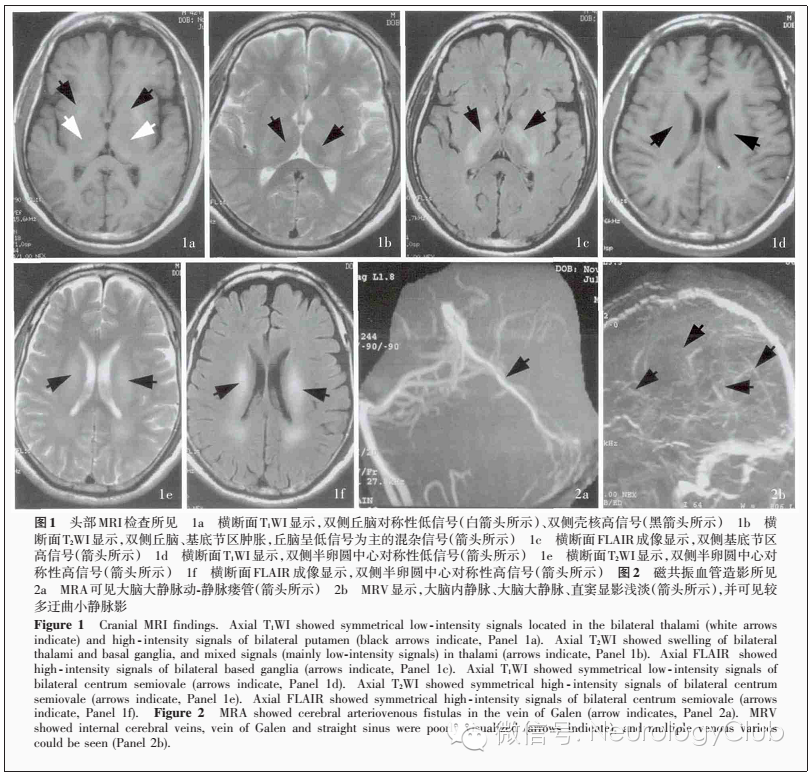

入院后进一步完善相关辅助检查。实验室检查:血尿便常规、肝肾功能试验、血清电解质、凝血功能试验、感染四项均正常;空腹血糖6.60mmol/L(3.60-6.10mmol/L),甘油三酯2.36mmol/L(0.45-1.70mmol/L)、高密度脂蛋白胆固醇0.87mmol/L(0.93-1.81mmol/L)、低密度脂蛋白胆固醇4.01mmol/L(2.07-3.63mmol/L)。腰椎穿刺检查脑脊液压力170mmH2O(80 -180mmH2O,1mmH2O=9.81×10^-3 kPa),葡萄糖4.80mmol/L,其余各项指标均正常;脑脊液寡克隆区带(OB)、抗神经节苷脂抗体GM1、髓鞘碱性蛋白(MBP)抗体和 Ho-Yo-Ri抗体均呈阴性;脑脊液弓形虫+风疹病毒+巨细胞+单纯疱疹病毒(TORCH)试验、快速血浆反应素试验(RPR)、梅毒螺旋体明胶凝集试验(TPPA)均无异常。 血清红细胞沉降率、C-反应蛋白、免疫球蛋白、补体、抗核抗体(ANA)谱、抗可提取性核抗原(ENA)抗体谱、抗中性粒细胞胞质抗体(ANCA)均呈阴性。血、尿有毒物质筛查无异常。血清维生素B12>1521pg/ml(200-893pg/ml)、叶酸>20 ng/ml(>3pg/ml),同型半胱氨酸水平正常、血氨水平36.6μmol/L,甲状腺功能和甲状腺相关抗体正常。甲胎蛋白(AFP)、前列腺特异抗原(PSA)、癌胚抗原(CA)等肿瘤标志物筛查未见异常,血清Hu-Yo-Ri抗体呈阴性反应。神经电生理学检查:脑电图显示,双侧脑前部导联可见较多慢波和电活动。影像学检查:腹部B超显示轻度脂肪肝,前列腺B超未见异常。胸部X线(正位)显示双肺纹理增多、紊乱,左下肺纤维条索影。头部MRV呈右侧引流优势,左侧横窦和乙状窦纤细,大脑内静脉、大脑大静脉、直窦显影浅淡伴较多迂曲小静脉影,考虑深静脉栓塞可能。头部MRI平扫显示,双侧半卵圆中心、放射冠、侧脑室旁、基底节区、丘脑对称性异常信号,双侧壳核短 T1信号,结合MRV表现,考虑静脉栓塞可能(图1);增强后病变区域未见明显异常强化。磁共振波谱(MRS)分析病变区域谱线异常,N-乙酰天冬氨酸代谢降低、胆碱代谢升高,并可见乳酸峰,提示为活动期病变。头部MRA与MRV检查显示大脑大静脉动-静脉瘘(图2)。脑血管造影检查可见大脑大静脉动-静脉瘘,动脉血供来自双侧颈内动脉系统、左侧颈外动脉系统和大脑后动脉,大脑大静脉血流逆向充盈,大脑内静脉、基底静脉、直窦显影欠佳。临床诊断:颅内动-静脉畸形。明确病因前予B族维生素营养神经,明确病因后转入介入科行动-静脉瘘栓塞治疗,术后予华法林3mg/次(1次/d)抗凝治疗,服药过程中监测国际标准化比值(INR)维持在2-3,并定期门诊随访。

神经科主治医师 该例患者为中年男性,呈亚急性发病、慢性病程。临床主要表现为嗜睡、缄默、反应迟钝、神情淡漠、记忆力减退、精神行为异常,疾病后期逐渐出现行走缓慢、双手摸索动作,大小便失禁,但无幻觉。既往有糖尿病、大量饮酒史,饮食以素食为主,较少食用肉类,家族史无特殊。神经系统检查神志清楚,表情淡漠,自发言语少,可简单对答,时间、人物定向力正常, 地点定向力可,记忆力减退。脑神经无异常,四肢肌力5-级、肌张力略高,腱反射对称引出;双侧掌颌反射、Chaddock征阳性。浅深感觉、共济运动正常,步基宽、呈小碎步。头部MRI显示双侧半卵圆中心、侧脑室旁、基底节区、丘脑对称性长T2信号,扩散加权成像(DWI)高信号;腰椎穿刺脑脊液压力正常,常规、生化正常;甲状腺功能和甲状腺相关抗体呈阴性。定位诊断:反应迟钝、神情淡漠、记忆力减退、自发言语少、精神行为异常等高级智能减退,定位于广泛性大脑皮质或皮质下白质;双侧掌颌反射、Chaddock征阳性,定位于双侧锥体束;行走姿势异常、小碎步、向后倾、四肢肌张力增高,定位于锥体外系;双手摸索动作提示双侧额叶损害可能;结合影像学所见,病变定位于双侧基底节区(丘脑、壳核、内囊)、半卵圆中心、放射冠定性诊断:该例患者为中年男性,亚急性发病,病程4-5个月 ,表现为高级智能下降、精神行为异常,影像学提示双侧基底节区、半卵圆中心、放射冠对称性损害,结合头部MRA、MRV和脑血管造影检查证实存在硬脑膜动-静脉瘘,故硬脑膜动⁃静脉瘘诊断明确。